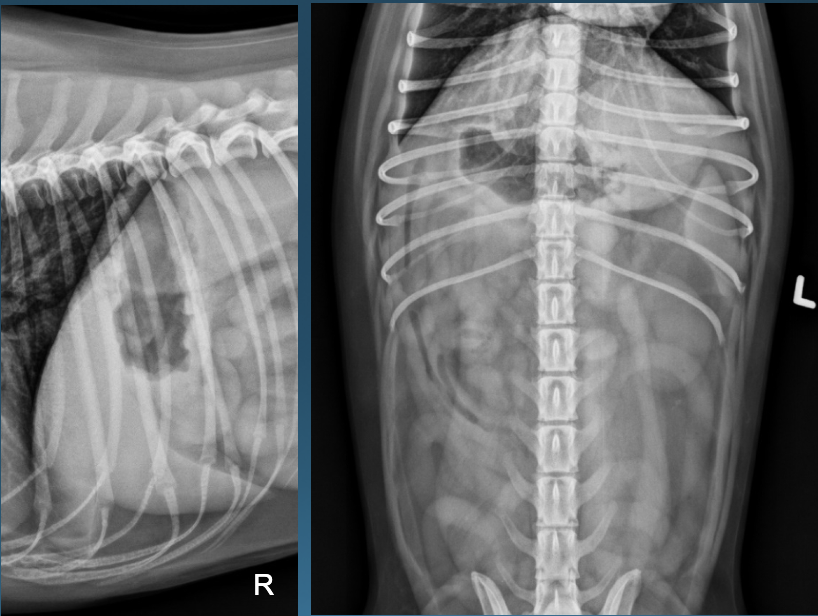

What is shown in these images?

A

*generalized hepatomegaly:

-extends past costal arch

-gastric axis no longer parallel with ribs; pylorus pushed caudal